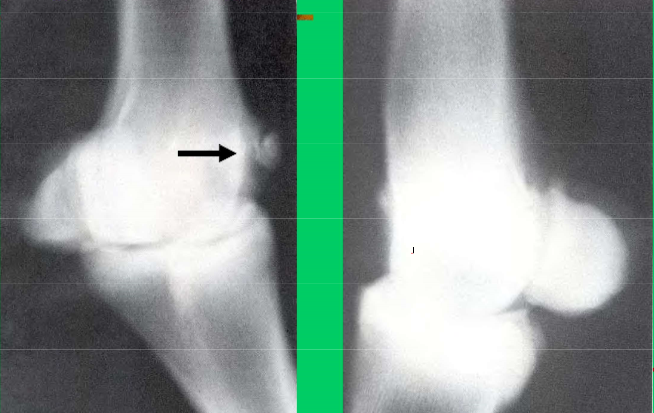

What is the location and lesion

This is an OCD cyst in the medial condyle of a horses femur- the only reported location